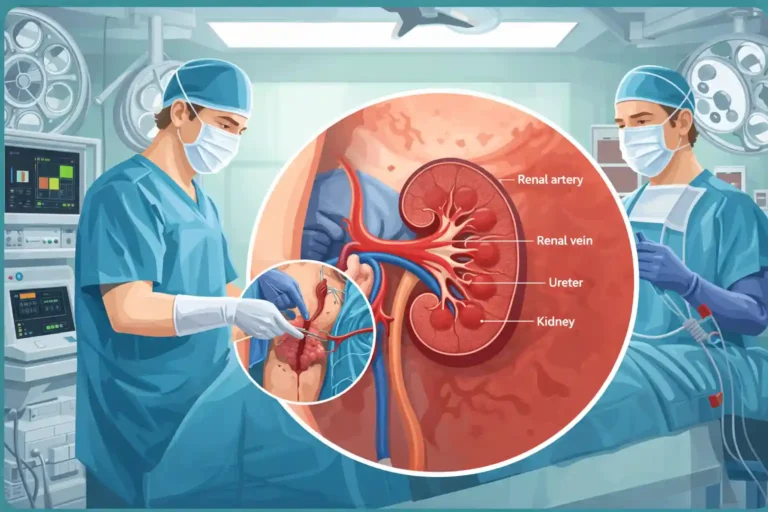

Step 2 – Diagnostic Evaluation

We conduct necessary blood tests, organ function tests, and imaging studies to assess your condition and ensure safety.